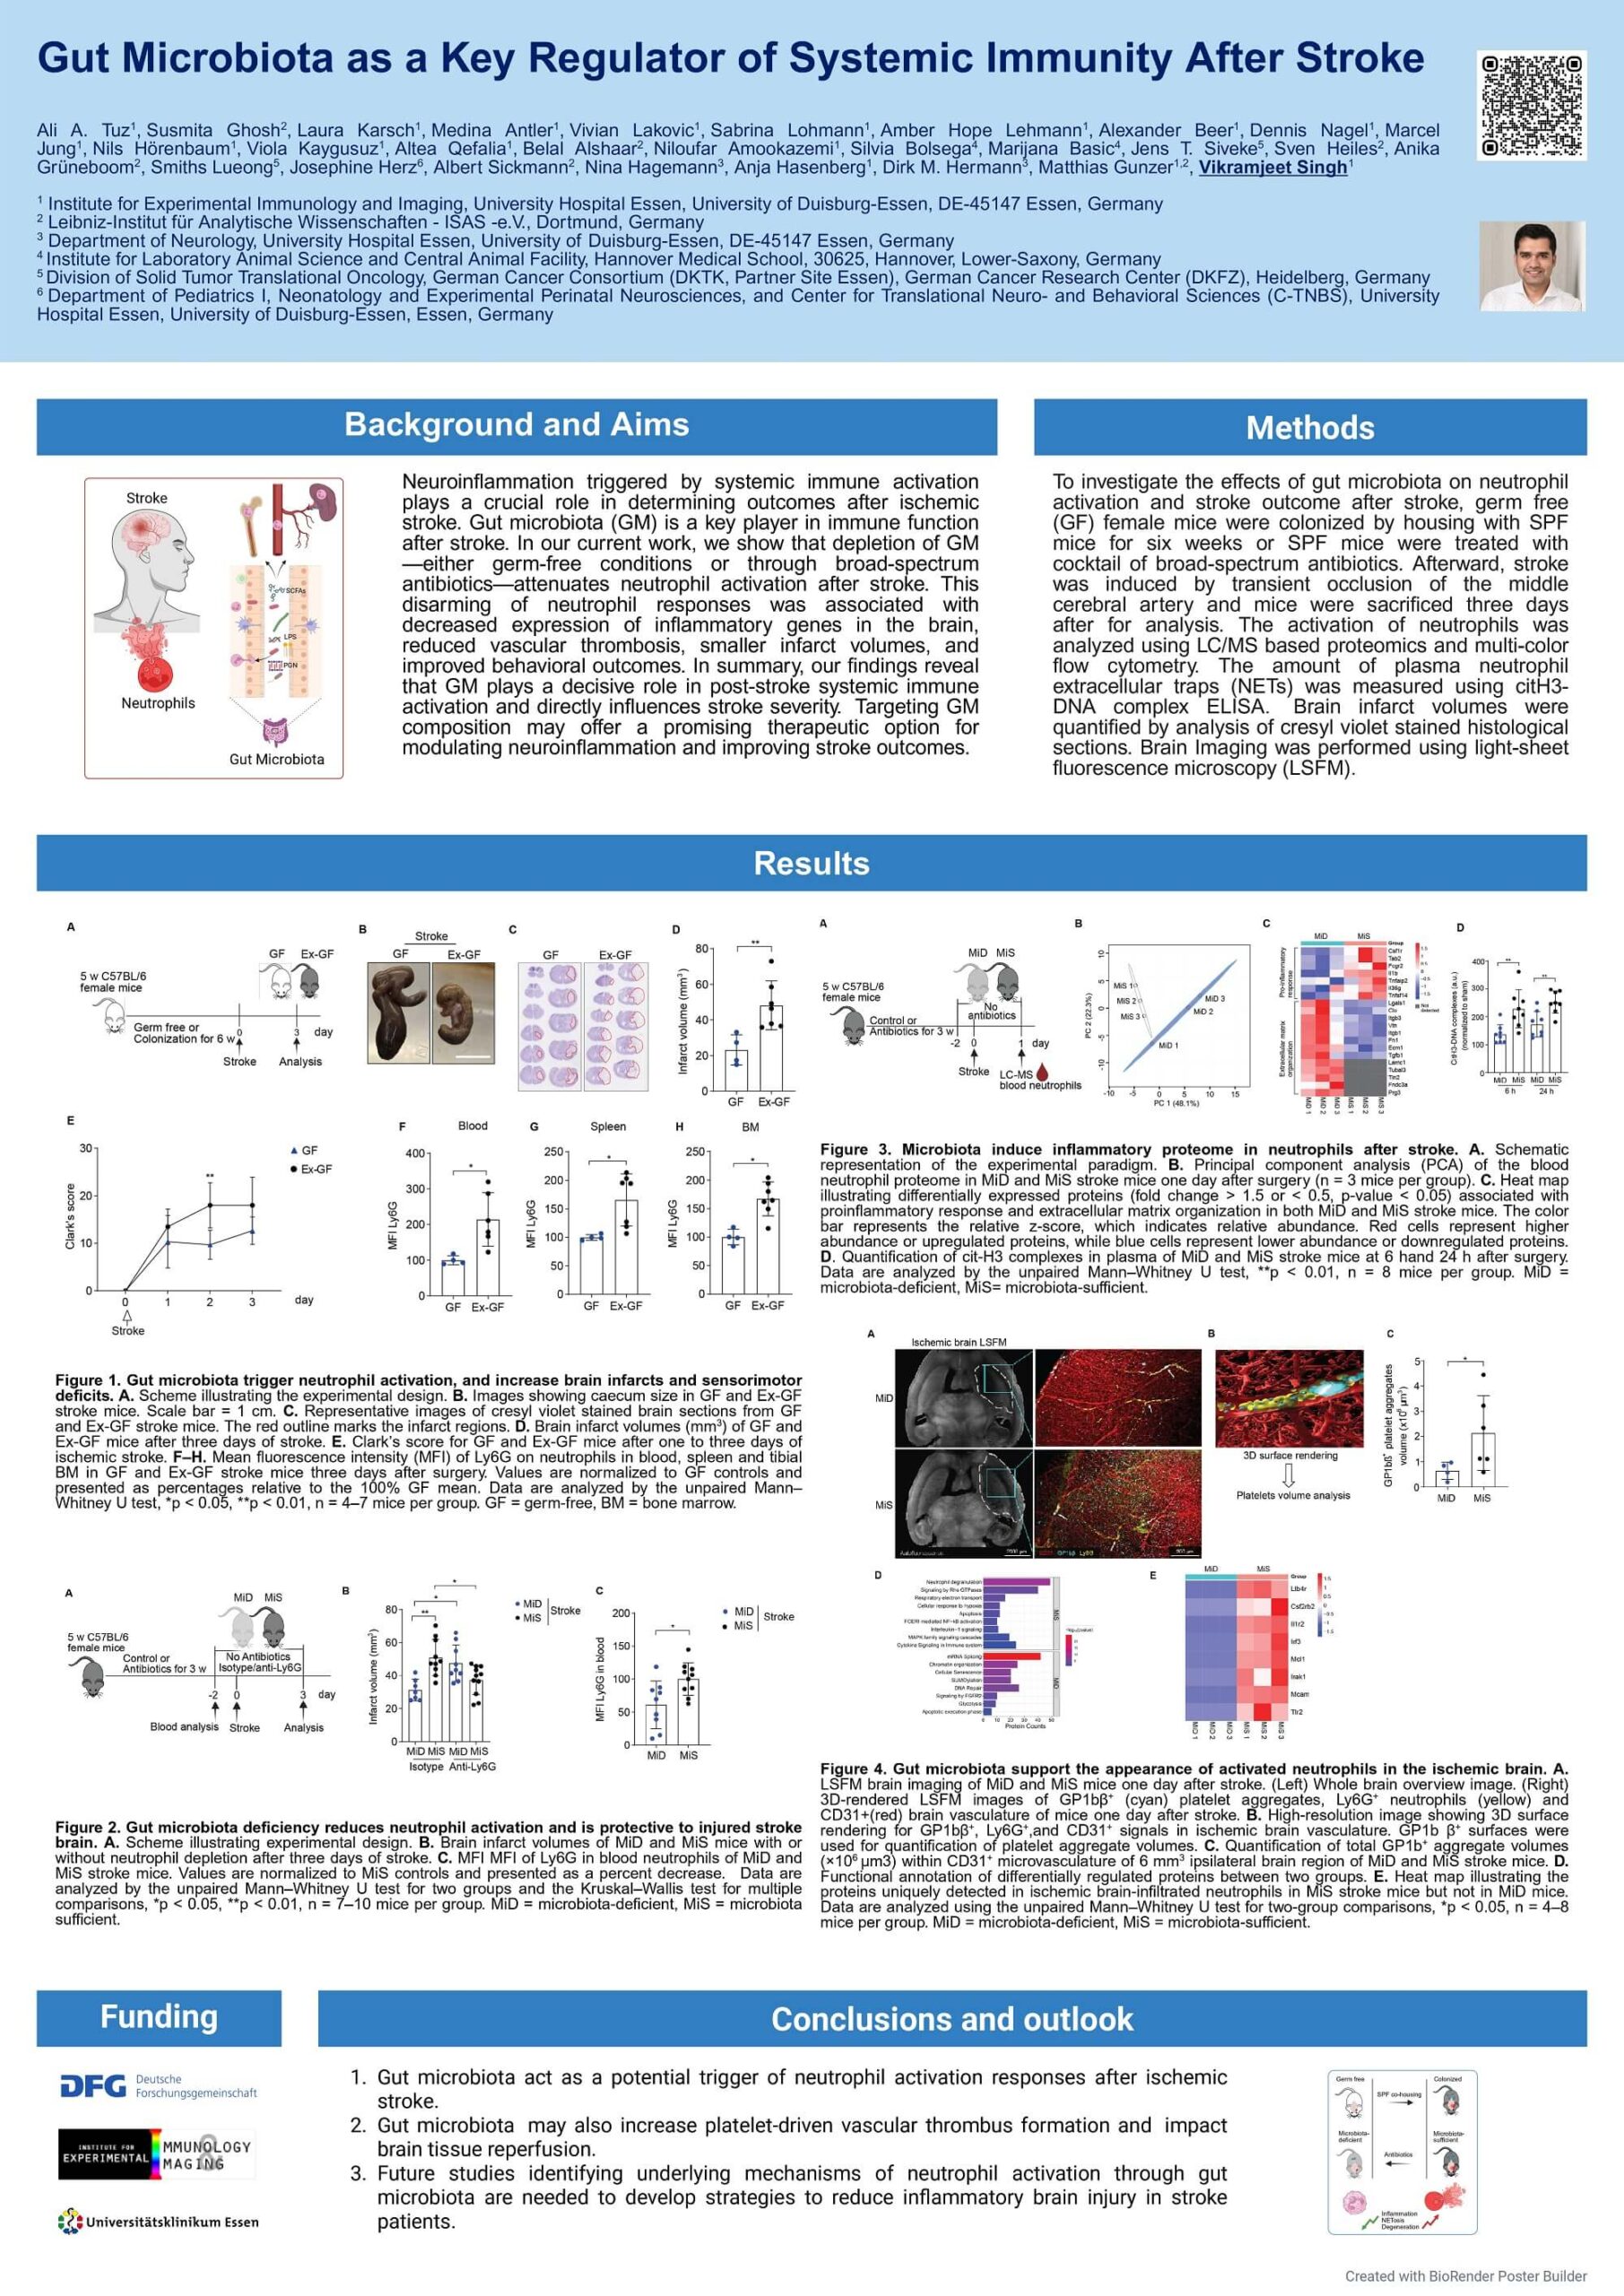

1. Tuz A, Ghosh S, Karsch L, Antler M, Lakovic V, Lohmann S, Lehmann A, Beer A, Nagel D, Jung M, Hörenbaum N, Kaygusuz V, Qefalia A, Alshaar B, Amookazemi N, Bolsega S, Basic M, Siveke J, Heiles S, Grüneboom A, Lueong S, Herz J, Sickmann A, Hagemann N, Hasenberg A, Hermann D, Gunzer M, Singh V. Gut microbiota deficiency reduces neutrophil activation and is protective after ischemic stroke. J Neuroinflammation 2025 May. With DFG funding.

2. Medina Antler, Heinrich-Heine-University, Düsseldorf ((M.Sc. 2024), “To understand the contribution of microbiota-dependent neutrophil activation on stroke outcome using germfree and antibiotic-treated mouse models“.

3. Vivian Lakovic, Heinrich-Heine-University, Düsseldorf (M.Sc. 2024), “To investigate the impact of intestinal microbiota on neutrophil activation and brain microvascular thrombus

formation using mass spectroscopy and light-sheet fluorescence microscopy“.